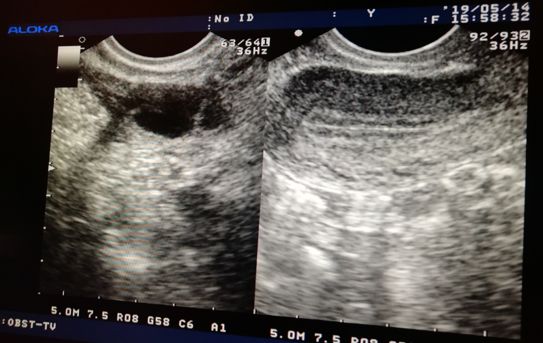

超声监测法是准确可靠的,它最能客观反映卵泡生长发育状况,观察是否有排卵,并同步反映子宫内膜的发育状况。

而且 阴道超声相对于腹部超声监测排卵更好,因为阴道超声探头更接近子宫和卵巢,分辨率高,更准确。

怎么判断卵泡长得好不好?

1、“身高”要合适

成熟卵泡大小为18-25mm,卵泡太小就排卵不易受孕,就算受孕也可能发育不良甚至流产;卵泡过大不破裂,失去排卵功能,会发生黄素化。

2、“体型”要圆润

优势卵泡一般都比较圆润、饱满,如果扁扁的,无膨胀感,就提示卵泡发育不太好。